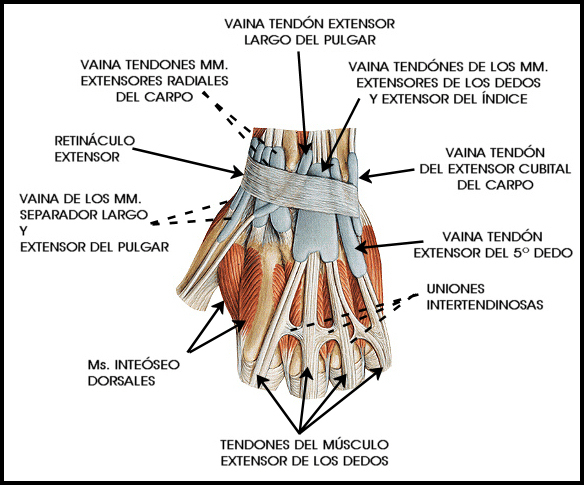

Por el dorso de la muñeca 12 tendones cruzan esa articulación por debajo de un engrosamiento de la aponeurosis profunda del antebrazo, llamado retináculo extensor, el cual divide los tendones en 6 pequeños compartimentos e impide su arqueo durante la extensión de la muñeca.

La distribución tendinosa en las diferentes correderas extensora dorsales es:

> Primera: Abductor pollicis longus (APL) y extensor pollicis brevis (EPB).

> Segunda: Extensor carpi radialis longus (ECRL) y extensor carpi radialis brevis (ECRB).

> Tercera: Extensor pollicis longus (EPL).

> Cuarta: Extensor digitorum (ED) y extensor indicis (EI).

> Quinta: Extensor digiti minimi (EDM).

> Sexta: Extensor carpi ulnaris (ECU